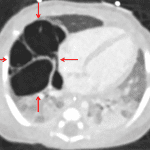

Findings

- Enteric tube tip overlies the gastric cardia

- Cystic structure in the right mid lung and right lung base

- Diffuse groundglass opacification throughout the left lung and in the right upper lung

- No pleural effusion or pneumothorax

- Normal size and configuration of the cardiothymic silhouette

Diagnosis

- Congenital pulmonary airway malformation (CPAM)

Enteric tube tip overlies the gastric cardia.

Cystic structure in the right mid lung and right lung base, which may represent a congenital pulmonary airway malformation (CPAM). Recommend chest CT for further evaluation.

Diffuse groundglass opacification throughout the left lung and in the right upper lung, which may relate to volume loss or edema.

No pleural effusion or pneumothorax.

Normal size and configuration of the cardiothymic silhouette.